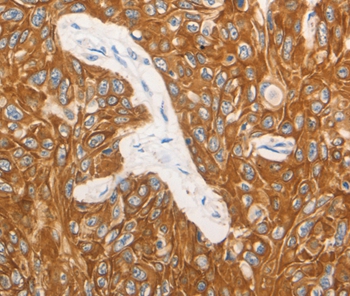

Immunohistochemical analysis of paraffin-embedded Human esophagus cancer tissue using #36895 at dilution 1/15.